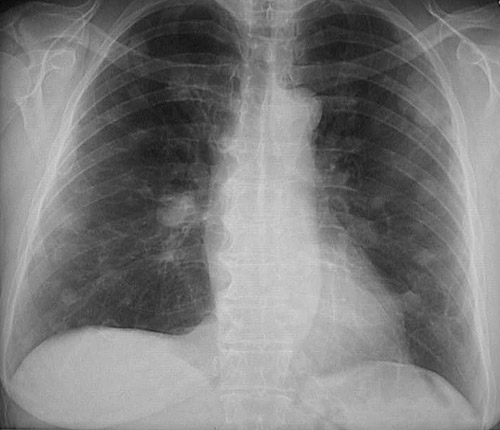

This chest radiograph reveals the presence of multiple rounded masses in all lung fields. These are metastases.